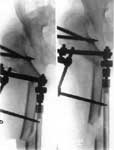

1.Врожденный вывих правого бедра, состояние после операции.

2.Операция Шанца-Илизарова с удлинением бедра.

3.Результат лечения.